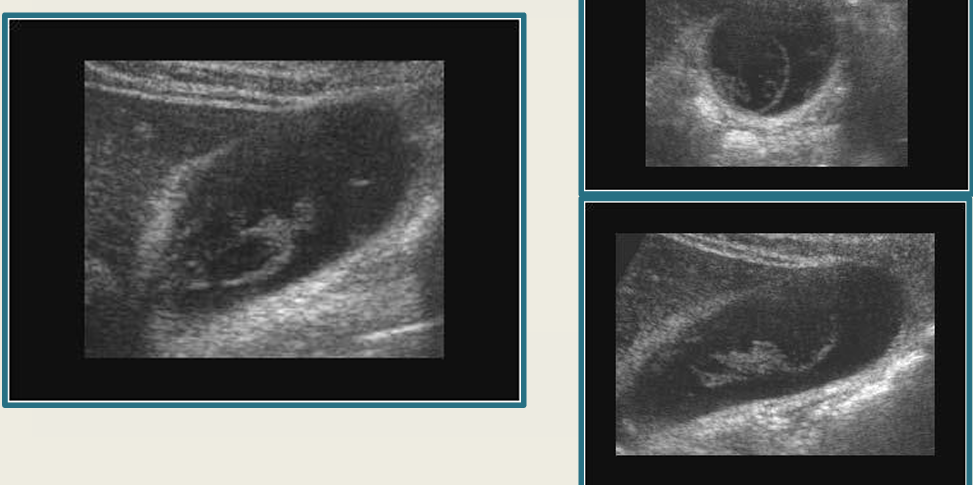

term image

cholelithiasis

WES sign